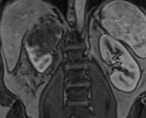

Robot-assisted laparoscopic nephroureterectomy for urothelial carcinoma with inferior vena cava incision and repair

Richard B Knight and Cristian P Ilie

Journal of Surgical Case Reports, Volume 2019, Issue 4, April 2019, rjz134, https://doi.org/10.1093/jscr/rjz134